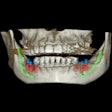

Air Techniques partners with SICAT for implant therapy